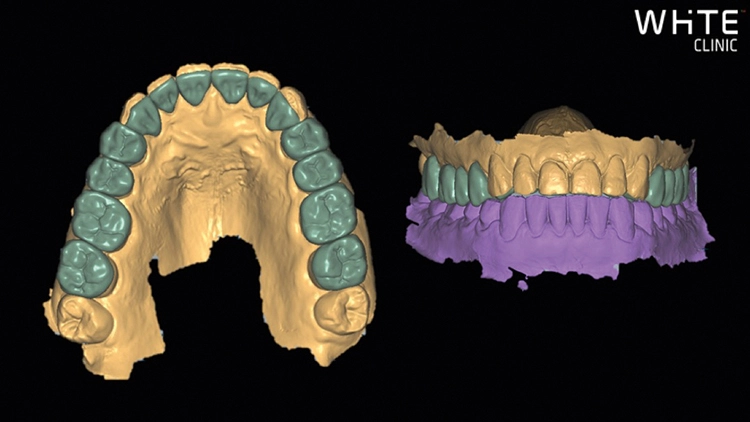

Fall 4: Verbreiterung seitlicher Schneidezähne

Entgegen dem Fall 3, bei dem bei gegebenen approximalen Platzverhältnissen eine Umformung primär durch eine Verlängerung der klinischen Zahnkronen gefordert war, imponieren im 4. Fallbeispiel bei einer 17-jährigen Patientin approximal Lücken der unverhältnismäßig schmalen, aber in ihrer Länge völlig ausreichend dimensionierten seitlichen Schneidezähne in Richtung der beiden mittleren Schneidezähne (Abb. 25 und 26). Im Vorgespräch und mithilfe eines intraoralen Mock-ups kam man überein, die beiden Zähne 12 und 22 lediglich nach mesial zu verbreitern. Ein diskreter Materialauftrag jeweils distal wäre zwar eine Option gewesen, würde dann aber wahrscheinlich die recht spitzen Eckzähne dominanter zum Vorschein treten lassen als jetzt. Prof. Dr. Ernst

Es war keine weitere Präparation erforderlich; lediglich die Schmelzklebeflächen wurden mit einer EVA-Feile (Proxoshape Flexible, Intensiv, Montagnola, Schweiz) gereinigt und leicht angeraut. Die Abbildungen 27 und 28 zeigen die vorbereitende Verschalung (Composi-Tight 4,6 mm Prämolaren Matrizenband, B-Serie, Garrison, Clip Flow, VOCO) und die Abbildungen 29 und 30 die bereits polymerisierte, diskrete Flow-Kompositmenge approximal-zervikal. Prof. Dr. Ernst